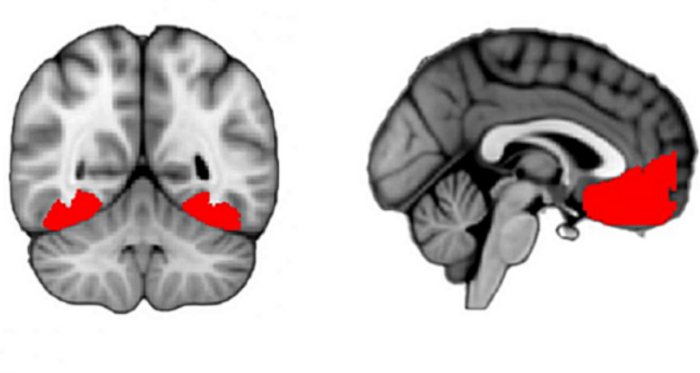

Using fMRI, researchers observed brain activity as subjects viewed texforms. The scans revealed high activity in the occipitotemporal cortex (OTC), a region above the ears involved in vision and object recognition. Previous studies suggested that clear images would show distinct OTC activity patterns for animate and inanimate objects.

Human brain-scan images show regions toward the back and front that are active for a person who is feeling curious. (Credit: Gottlieb Lab/Columbia’s Zuckerman Institute)